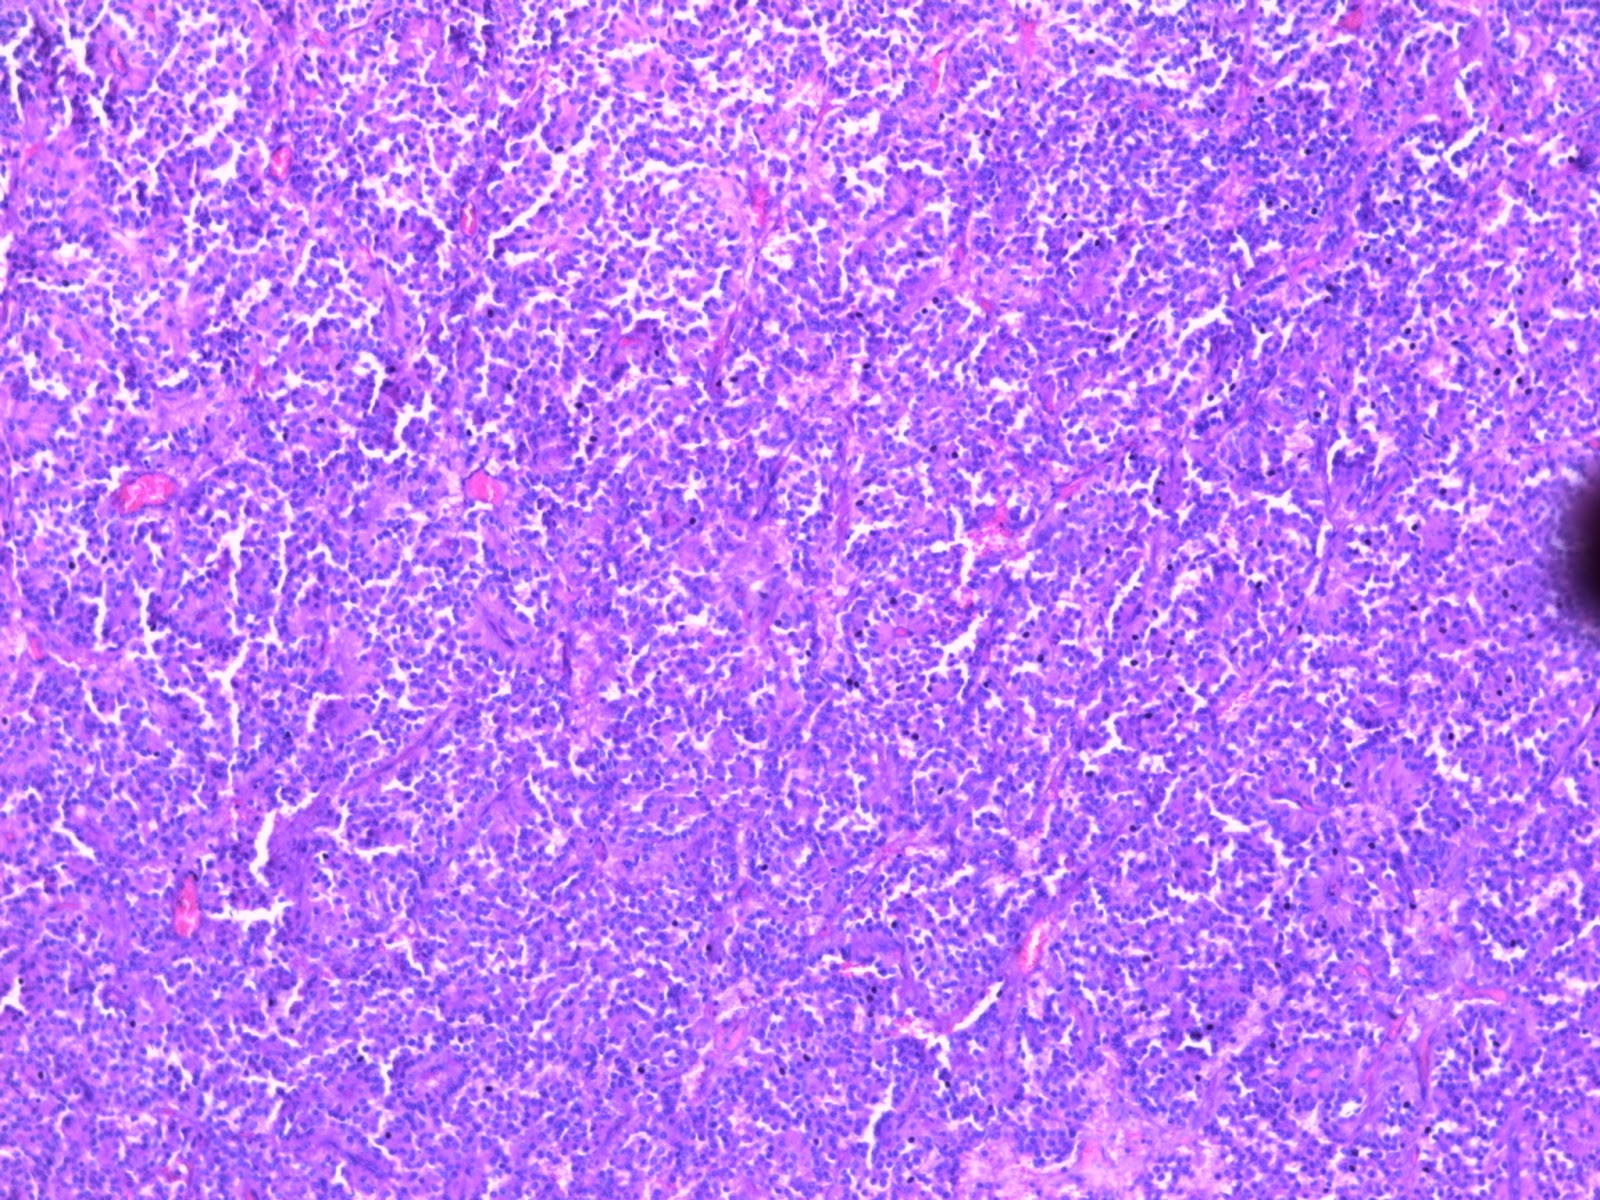

Der Begriff Tumor-Metabolom beschreibt den charakteristischen Stoffwechsel-Phänotyp (= das Metabolom) von Tumorzellen.

Die Umwandlung von normalen Zellen in Tumorzellen ist mit einschneidenden Veränderungen im Stoffwechsel der Zellen verbunden.

Intensive Stoffwechsel-Charakterisierungen (Metabolom-Analysen) von verschiedenen Tumor-Zelllinien und Tumoren haben ergeben, dass sich während der Tumorentstehung bei bestimmten Stoffwechsel-Parametern immer die gleichen Stoffwechsel-Änderungen einstellen.